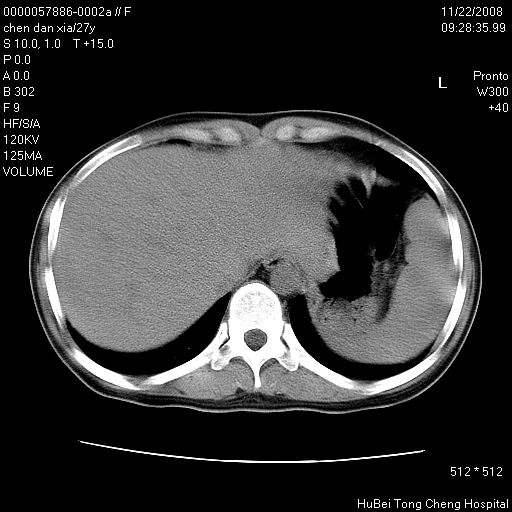

标题: CT16752:F,27Y。发热咳嗽20余天,伴盗汗。 [打印本页]

标题: CT16752:F,27Y。发热咳嗽20余天,伴盗汗。

右下肺见片絮状影,两肺野内分布不均的小结节影,结核并肺内播散可能性大,建议结合实验室检查 .

双肺纹影普多,部分呈网状,支炎或淋巴管炎?

纵隔内淋结肿

局部胸膜增厚

右侧前胸壁胸膜局限性肥厚(胸膜炎?)其他的强化观察.

1)考虑两肺感染性病变。2)纵隔淋巴结肿大。

建议:抗炎治疗后复查。